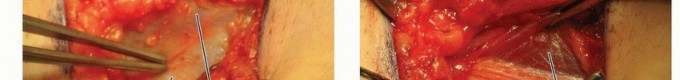

Modified Smith-Petersen Anterior Approach

The entire hip and lower extremity is draped free so that the hip joint can be moved through a full range of motion.

The incision is a modification of the classic Smith-Petersen approach with a cosmetic and limited incision in the groin, centered just below the anterior superior iliac spine (ASIS) ( TECH FIG 1A ).

Sharp knife dissection is used to the deep fascia. The incision is continued until no more fat is apparent and the deep fascia is exposed.

A sponge is used to separate the distal flap from the deep fascia.

There is a small interval of fat between the tensor and sartorius muscles several centimeters distal to the ASIS ( TECH FIG 1B ). The surgeon should incise slightly lateral to the fat on the fascia of the tensor.

Army-Navy retractors are used to separate this internervous interval until the rectus femoris muscle is visualized.

A Kittner sponge is used on the lateral edge of the rectus femoris muscle, and the surgeon dissects along this edge proximally until the reflected head of the rectus femoris muscle is exposed ( TECH FIG 1C ).

Just lateral to the reflected head is the hip capsule, which is covered with fat.

The fat is reflected to expose the hip capsule. The reflected head of the rectus femoris muscle may be divided for better exposure of the hip capsule.

It is best to visualize a large area of the hip capsule for better orientation before making an incision into it.

The capsule is incised with a no. 15 blade.

A 3-mm, 45-degree Kerrison rongeur is useful to remove several millimeters of the anterior capsule for continued postoperative decompression ( TECH FIG 1D ).

The joint is irrigated with saline through a large-bore intravenous catheter placed deep within the joint. A suction drain is placed for several days after surgery until there is only minimal drainage.

The skin is closed loosely with interrupted nylon sutures to allow potential drainage.

Closing the deep fascia increases the risk of reaccumulation.

TECH FIG 1 • Modified Smith-Petersen anterior approach to the right hip. A. The incision is placed in the anterior groin crease for best cosmesis. B. The tensor-sartorius muscle interval is identified distally where the muscles begin to separate. C. The reflected head of the rectus femoris muscle can be released to reveal the underlying hip capsule. D. A 45-degree Kerrison rongeur is used to enlarge the anterior hip capsulorrhaphy.